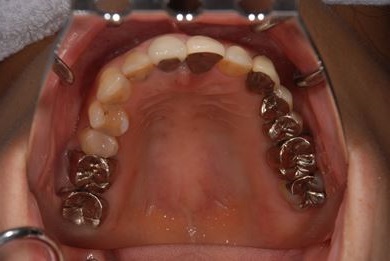

| 性別/年齢 | 女性 / 40歳 | ||||||||||||||||||||||||||||||||

| 治療方針 | 保存不能な歯を抜歯し、セラミック治療にて、機能的・審美的回復を行う。 | ||||||||||||||||||||||||||||||||

| 治療内容 | ジルコニアフレームオールセラミッククラウン7本(オールセラミック用土台3本)、ハイブリッドセラミッククラウン1本、ハイブリッドセラミックインレー1本 | ||||||||||||||||||||||||||||||||